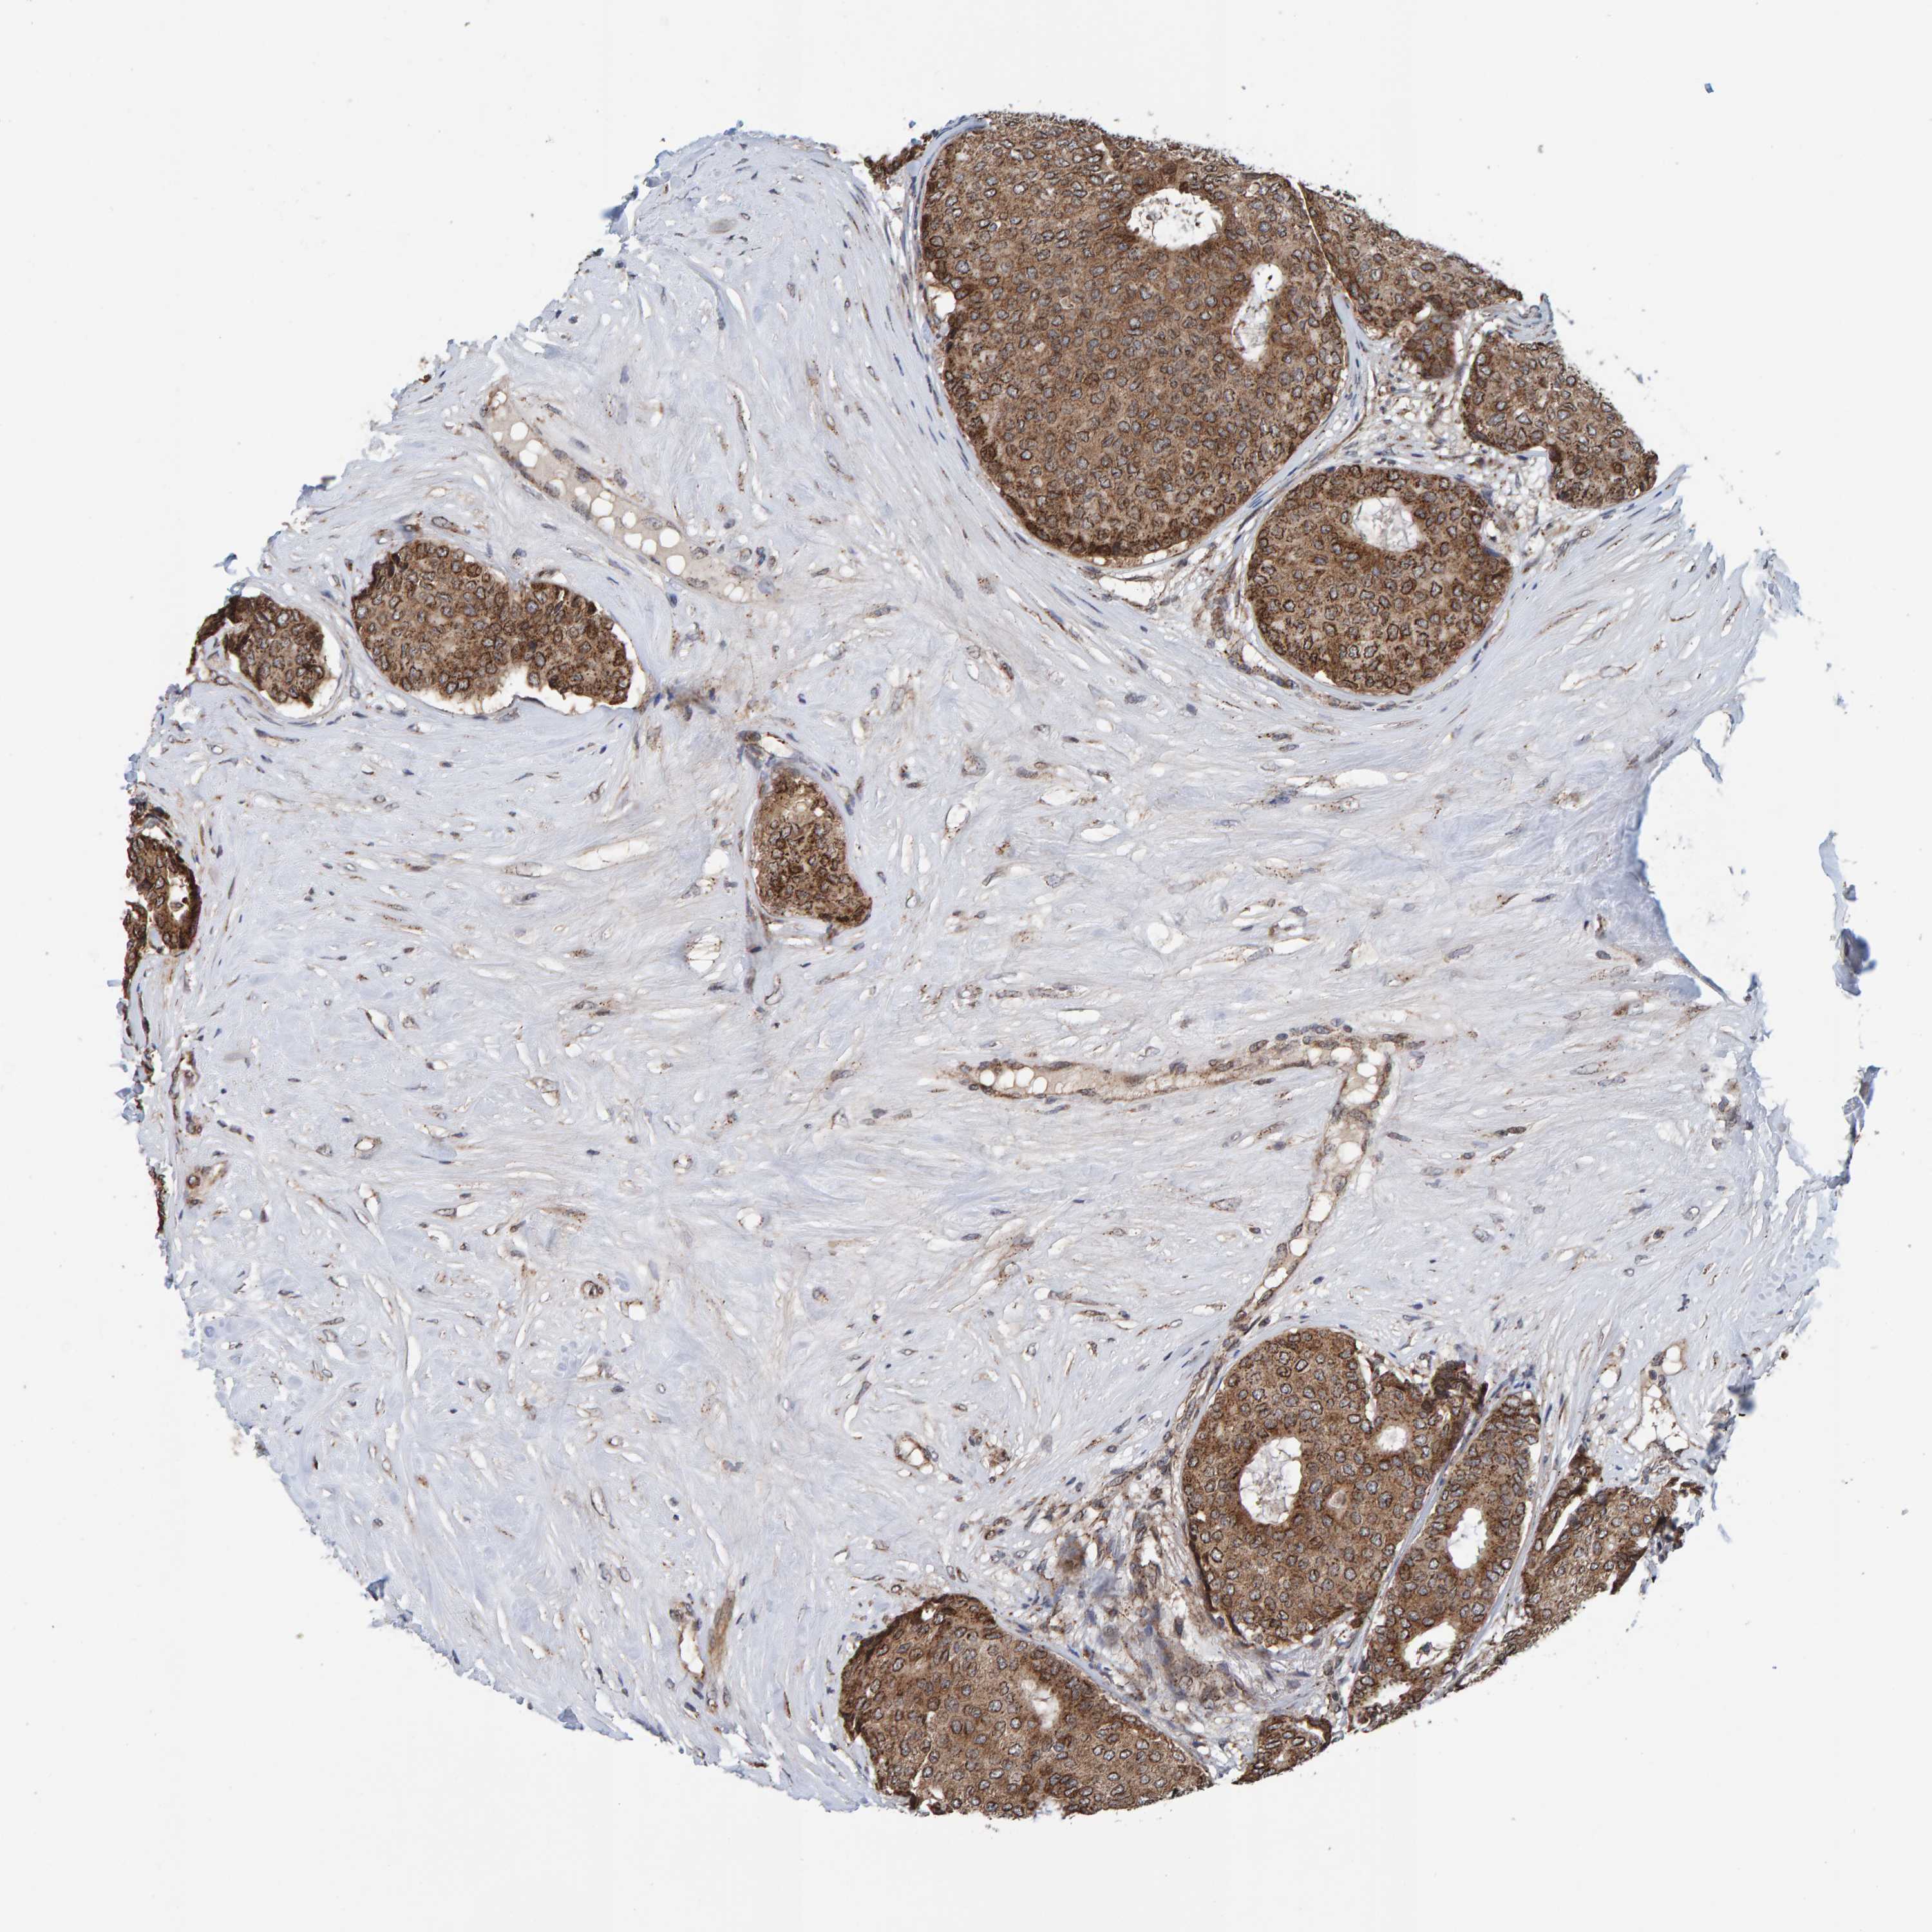

BRCA TCGA BRCA VALIDATION PROTEIN EXPRESSION

ANTIBODIES

AND

VALIDATION